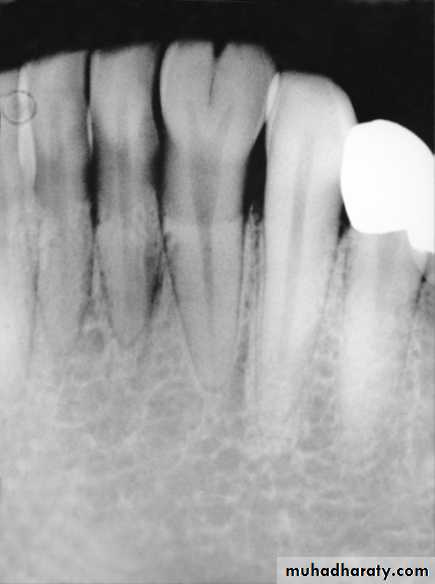

2. Dens in dentUpper lateral incisor with invagination